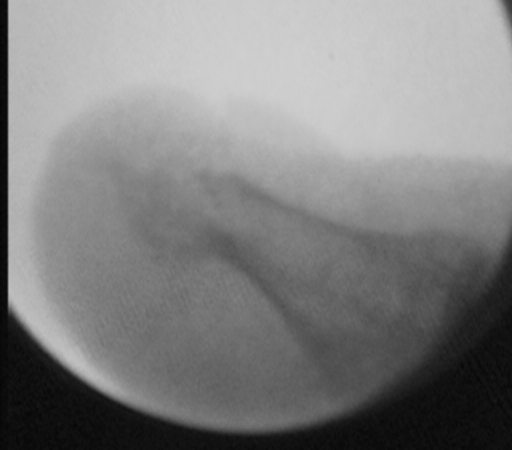

Imagen fluoroscópica de la eliminación de la exóstosis calcánea (espolón) por cirugía M.I.S